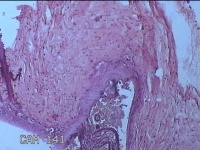

胎盘组织

胎膜早破 早产

停经36+1周,阴道流液3天。

灰白暗红色胎盘组织18x15.5x2.3㎝一个,表面光滑,血管清晰,颜色发暗,绒毛面结节状,轻度糜烂,表面有少许凝血块,切面见绒毛内有部分淤血,边缘蜕膜可见多个小血肿,脐带15x1.5x0.8㎝,切断脐带,见脐血管内有凝血块。